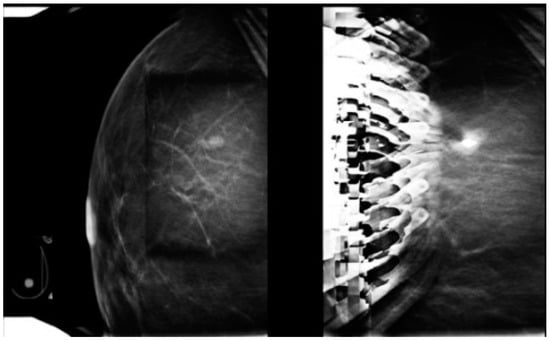

Figure 17. (a) A 65-year-old patient with a screen-detected left breast mass (circle). (b) Post-procedure mammograms after DBT-guided biopsy show the biopsy cavity and clip marker (dashed arrow) to be laterally located with respect to the mass (arrow). Pathology shows atypical ductal hyperplasia. Because of concern about proper sampling and radiological-pathological discordance, a surgical excision after wire localization was performed (c). Final pathology reveals a grade 1 invasive ductal carcinoma.